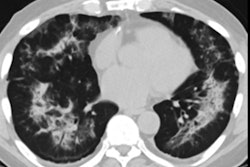

The FDA opened a docket on February 14 to obtain unpublished information related to the use of vaping products that are associated with electronic cigarette (e‑cigarette), or vaping, product use-associated lung injury (EVALI).

In January, the U.S. Centers for Disease Control and Prevention released a report announcing that lung disease linked to vaping likely was most prevalent in people who vaped THC-containing products obtained from informal sources, such as dealers, family, friends, and online. It is suggested that these factors and the presence of the compound vitamin E acetate in vaping products are strongly linked to the EVALI outbreak.